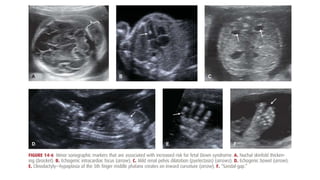

• Figure 14.6

• #20 Major abnormalities and minor sonographic markers contribute significantly to aneuploidy detection. As shown in Table 14-6, with few exceptions, the aneuploidy risk associated with any major abnormality is high enough to warrant offering an invasive test for fetal karyotype and/or chromosomal microarray analysis Importantly, a fetus with one abnormality may have others that are less likely to be detected sonographically or even undetectable sonographically but that greatly affect the prognosis nonetheless Most fetuses with aneuploidy that is likely to be lethal in utero—such as trisomy 18 and 13 and triploidy—usually have sonographic abnormalities that can be seen by the second trimester. However, only 25 to 30 percent of second-trimester fetuses with Down syndrome will have a major malformation that can be identified sonographically

• #21 For more than two decades, investigators have recognized that the sonographic detection of aneuploidy, particularly Down syndrome, may be improved by minor markers that are collectively referred to as “soft signs.” Minor markers are normal variants rather than fetal abnormalities, and in the absence of aneuploidy or an associated abnormality, they do not significantly affect prognosis Unfortunately, at least 10 percent of unaffected pregnancies will have one of these soft signs, significantly limiting their utility for general population screening The incorporation of minor markers into second-trimester screening protocols has been studied primarily in high-risk populations. In this setting, detection rates of 50 to 75 percent for Down syndrome have been reported (American College of Obstetricians and Gynecologists, 2013c). With the exception of increased nuchal skinfold thickness, the identification of an isolated second-trimester marker in an otherwise low-risk pregnancy is not generally considered sufficient to warrant “highrisk” status

• #23 Each has also been associated with an increased risk for trisomies 18 and 13 and other aneuploidies. However, these signs have not become widely adopted for routine use in the United States. Fetal Nasal Bone. In approximately two thirds of fetuses with Down syndrome, the nasal bone is not visible at the 11- to 14-week examination (Cicero, 2004; Rosen, 2007; Sonek, 2006). Currently, this is the only first-trimester marker, other than NT, for which the Nuchal Translucency Quality Review Program has established a training program. Criteria for adequate assessment include that the fetus occupies most of the image; that there be a 45-degree angle of insonation with the fetal profile; that the profile be well defined in the midsagittal plane, with the tip of the nose and the third and fourth ventricles visible; and that the nasal bone brightness be greater than or equal to that of the overlying skin